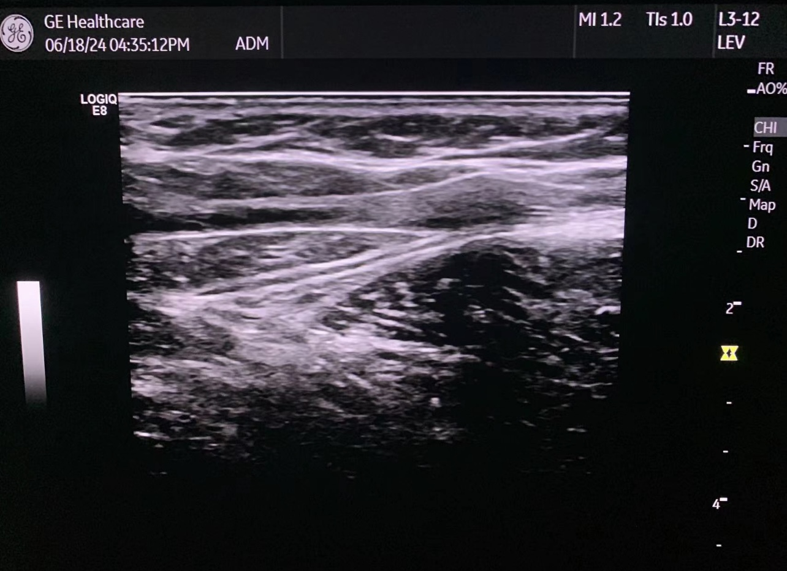

国内首例MOCA手术

2025年8月8日,浙江省人民医院完成了我国第一例MOCA手术。患者为90余岁高龄,心脏功能差,大隐静脉主干表浅,不适合热消融。术中通过4F鞘高速旋转破坏内膜后注入硬化剂,效果理想。